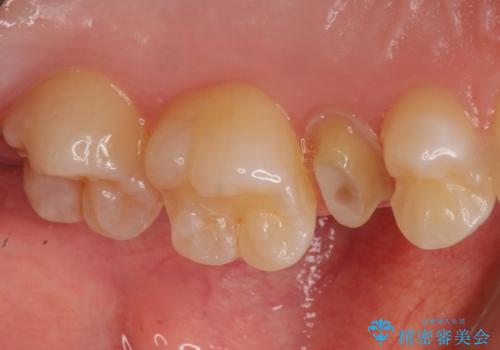

- 以前つけた被せ物がすぐにはずれてしまい1年以上放置してしまったことを主訴に来院された患者様です。

精査したところ、左上の小臼歯(左上5)は被せ物がないまま放置していたことにより、両隣の歯が寄ってきてスペースが少なくなり、また隣の歯(左上4)も虫歯になっていました。

隣の歯の虫歯治療(保険内のレジン充填)後、セラミッククラウンによる補綴を行いました。